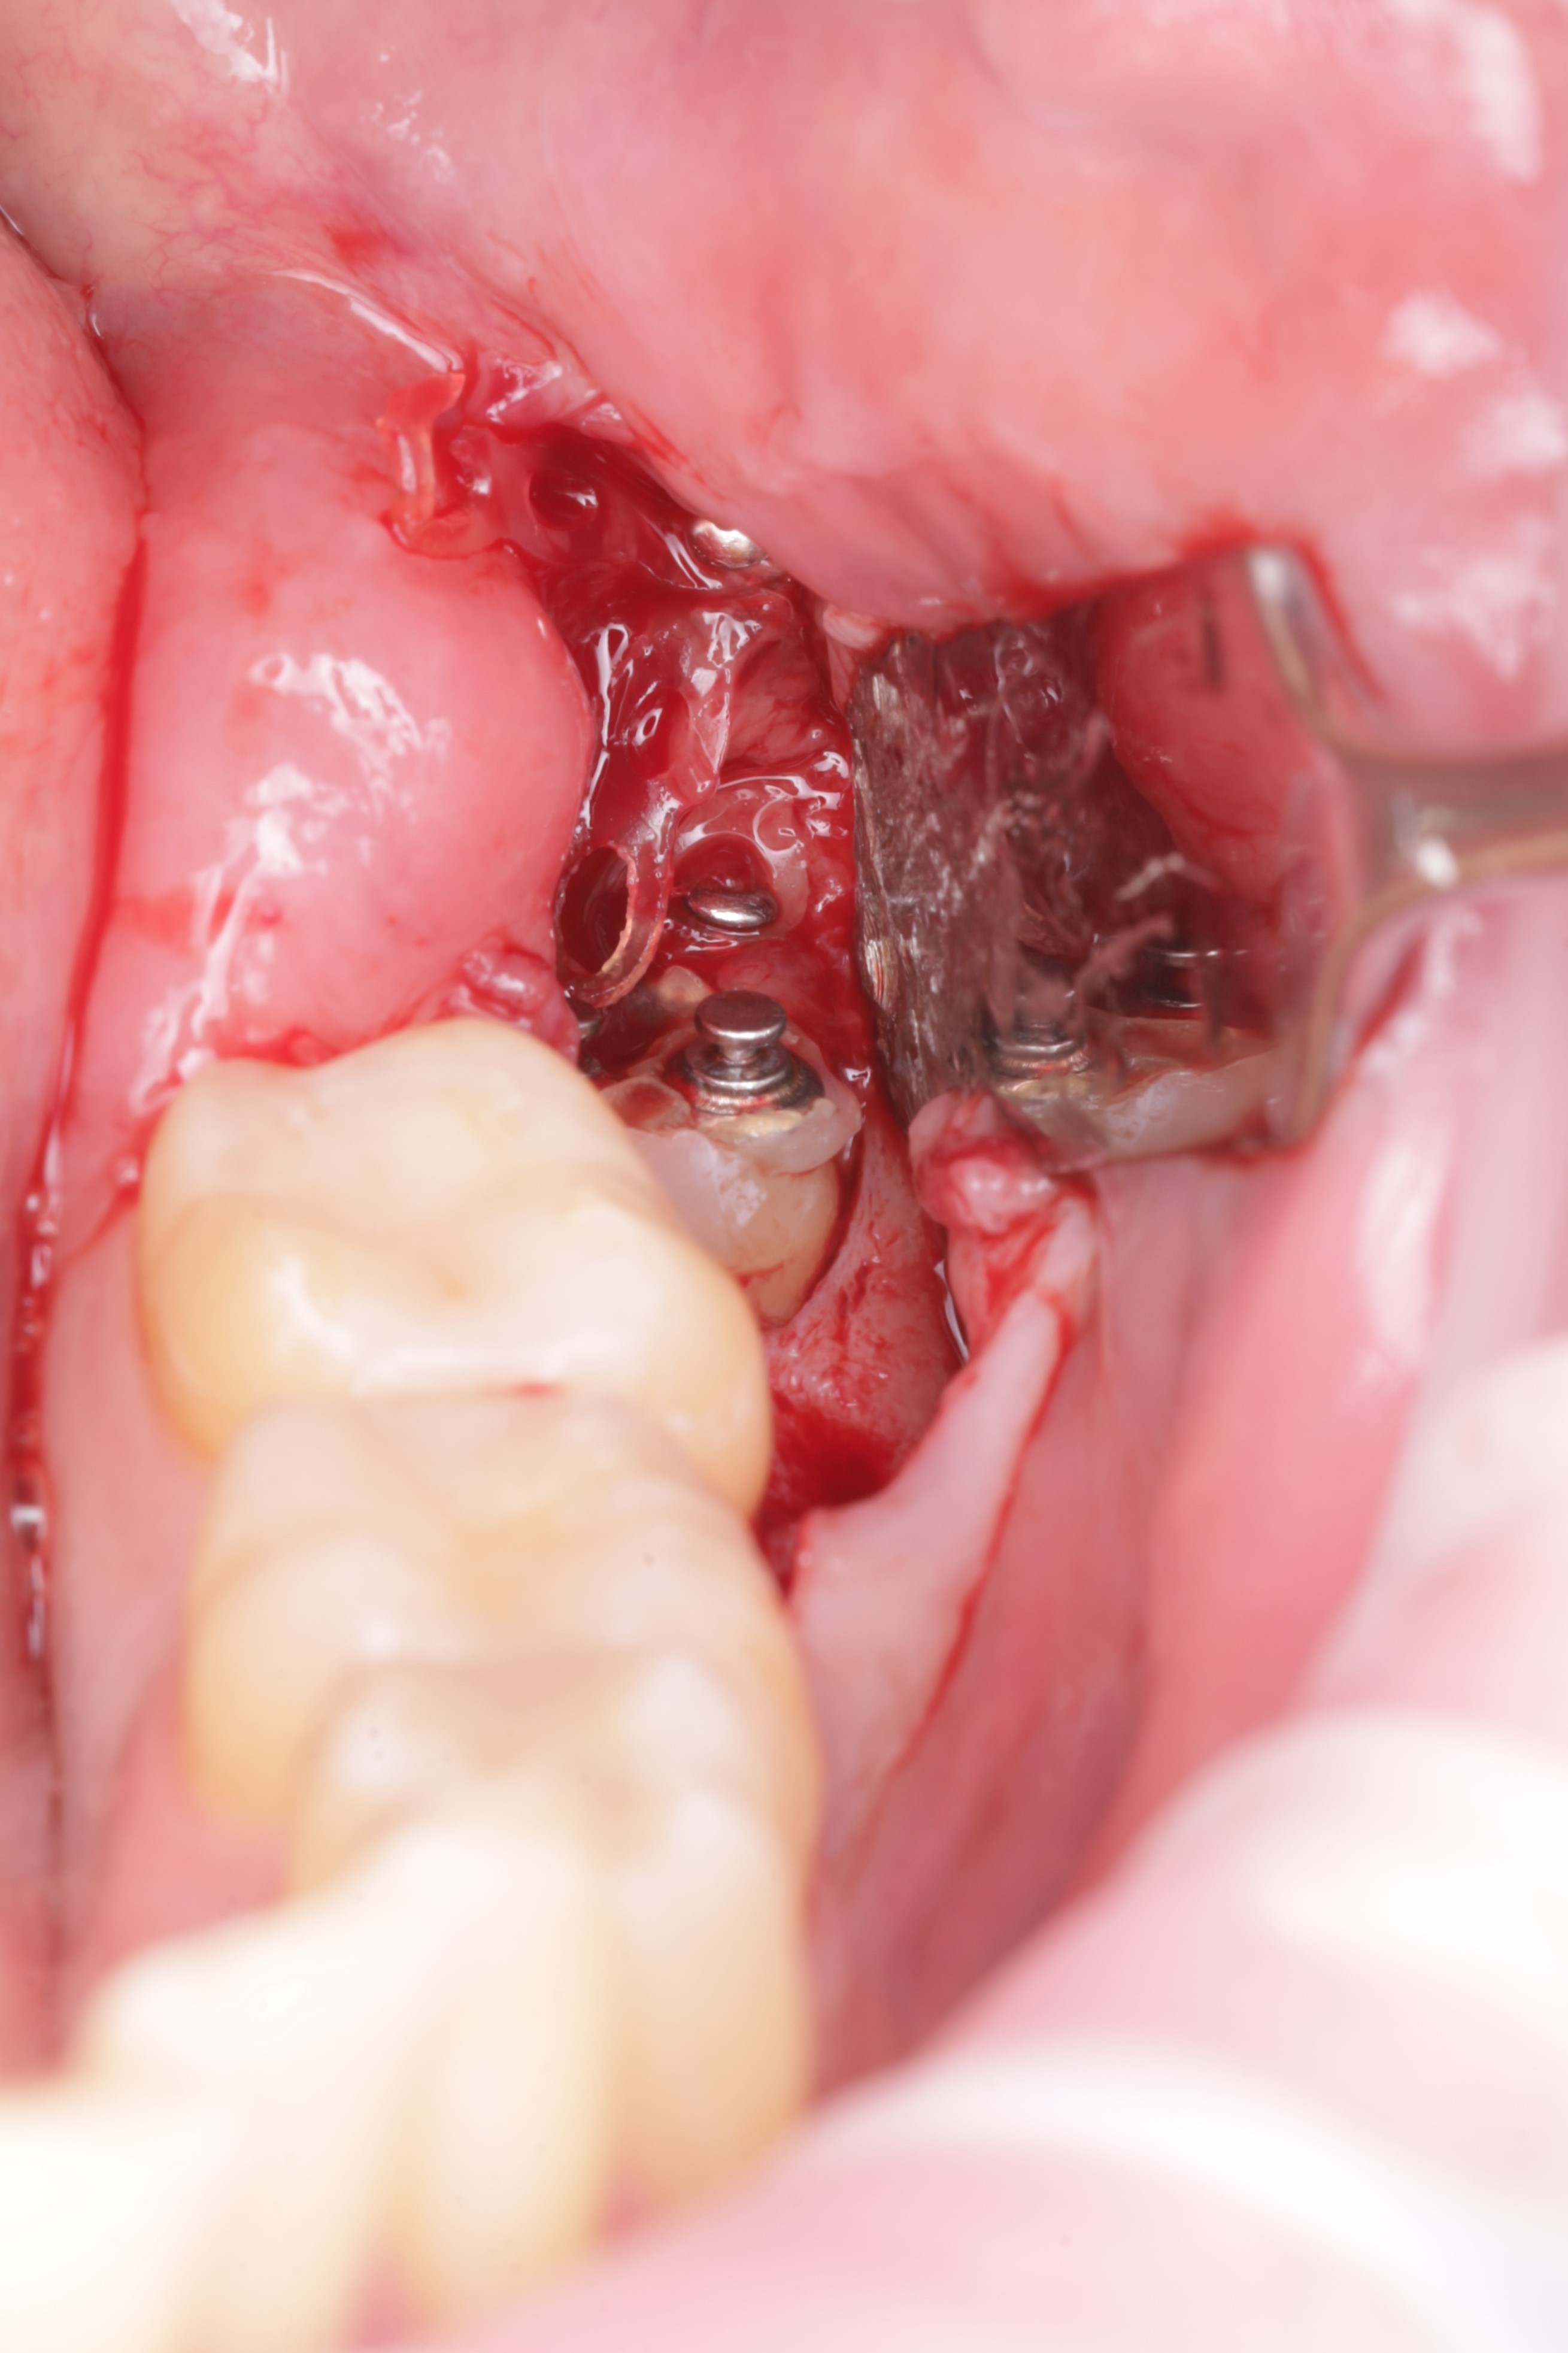

Аккуратно сформирован доступ к ретинированному зубу

Произведено иссечение тканей коронковой части зуба